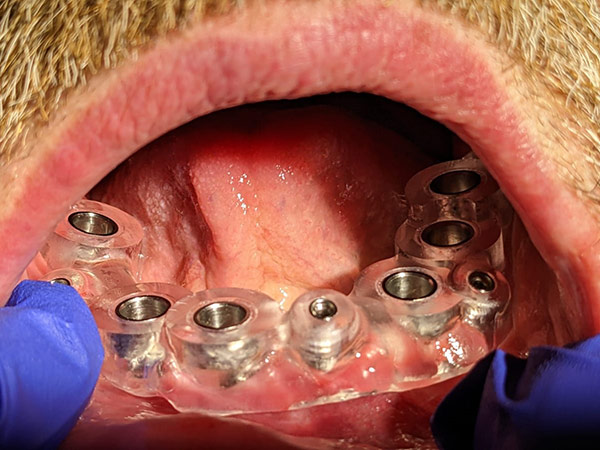

Sono state eseguite Tac con dima radiologica e progettazione per inserimento implantare tramite dima chirurgica di sei impianti AZ Implant tipo DX con overdenture a carico immediato.

L’intervento è stato eseguito dal Dr. Matteo Pini con dispositivi medici AZ Implant.